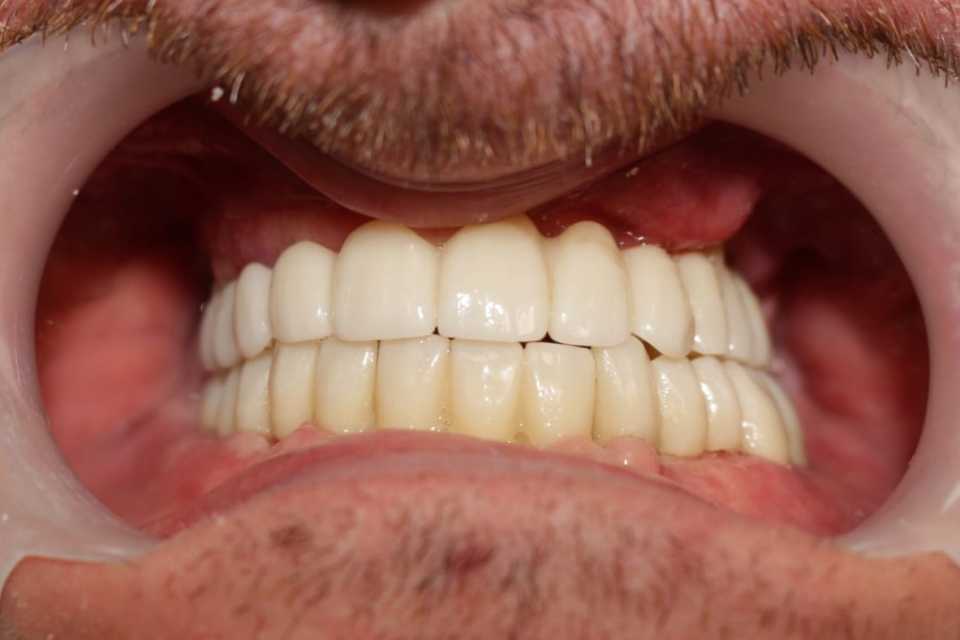

Reabilitarea orala funcțională și estetică, s-a realizat cu ajutorul unei lucrări fixe cimentate la nivelul maxilarului din ceramica pe zirconiu și a 3 lucrări din ceramica pe zirconiu fixe cimentate la nivelul mandibulei.

Cazul a fost o adevărată provocare, nu numai chirurgical, dar și protetic. Prin prisma resorbției osoase severe maxilare în zona frontală și a purtării îndelungate a protezelor mobile, la momentul consultului inițial, pacientul prezenta un etaj inferior al feței micșorat cu profil concav .